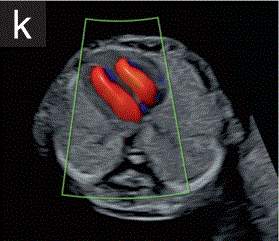

6.3 通过结合灰阶和彩色多普勒成像,可以更可靠地实现胎儿心脏的早期评估。

6.4 彩色多普勒有助于确认在舒张期存在两个不同的心室,并有助于排除明显的房室瓣反流(图2k)。

胎儿mt是什么检查什么疼吗【文献学习/规范指南】ISUOG实践指南(2023更新): 11-14周胎儿超声检查(全文)_https://www.jmylbn.com_新闻资讯_第18张

2 11+0至14+0周时,可作为详细胎儿超声检查的一部分获得的解剖图。

(k)采用彩色多普勒检查的胎儿心脏四腔切面,显示舒张压流分别从左右心房进入右心室和左心室。